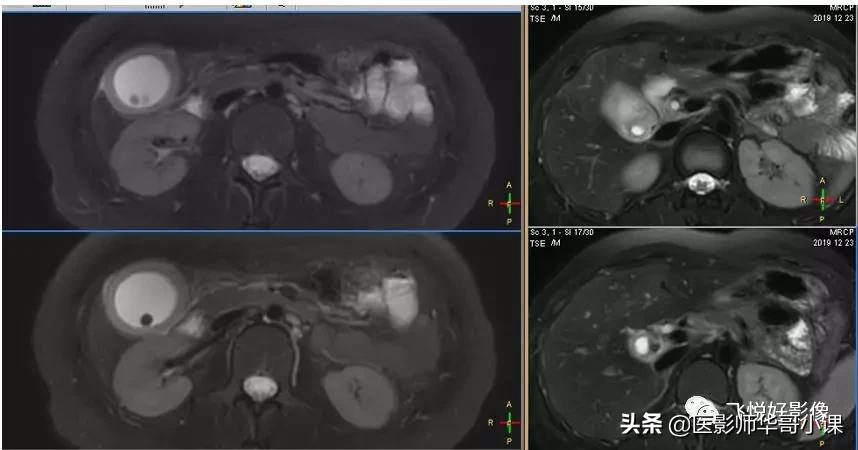

T2W示胆囊内多发结石,胆囊饱满。

T2WI_FS_TRA示:胆囊结石、胆囊壁明显增厚、胆囊窝少量积液

2D MRCP胆囊颈显示不清,无法重建。

3D_MRCP_BH可以进行3D重建,找到“责任病灶”。